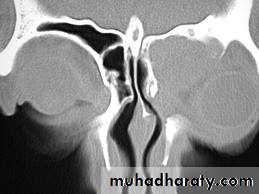

Radiology

Plain X- ray is out of use !CT Scan is the best imaging technique for the diagnosis of sinus problem.

21

CT scans of the paranasal sinuses should be reserved for:Patients in whom surgery is being considered as a management strategy

Patients who do not respond to medical regimes which include adequate antibiotic use

Assisting in diagnosis of anatomical changes interfering with airflow or drainage

Patients presenting with complications of sinusitis